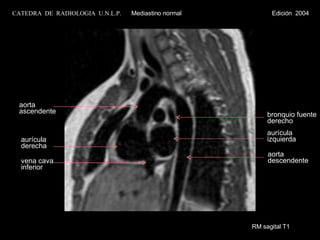

RM sagital T1 bronquio fuente derecho aurícula izquierda aorta ascendente aurícula  derecha vena cava inferior aorta descendente CATEDRA  DE  RADIOLOGIA  U.N.L.P.   Mediastino normal  Edición  2004

RM sagital T1bronquio fuente derecho aurícula izquierda aorta ascendente aurícula derecha vena cava inferior aorta descendente CATEDRA DE RADIOLOGIA U.N.L.P. Mediastino normal Edición 2004